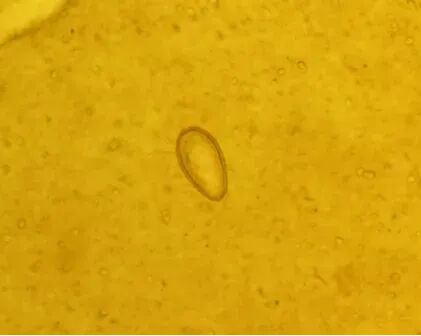

(肝吸虫卵)

肝吸虫病学名华支睾吸虫病,是由华支睾吸虫寄生在人体肝胆管内引发的食源性寄生虫病,主要因生食或半生食含肝吸虫囊蚴的淡水鱼虾感染,是典型的“病从口入”疾病。